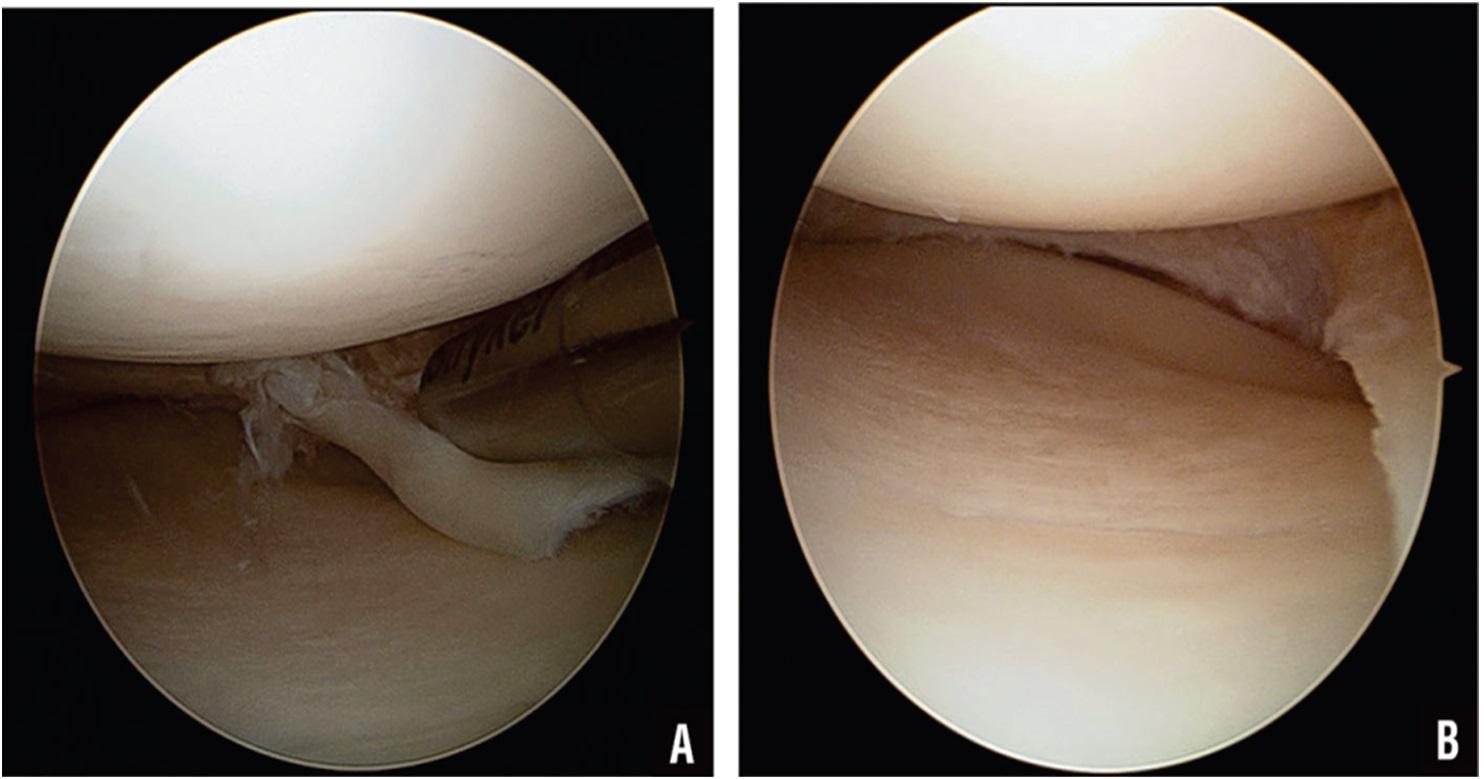

ARTHROSCOPY

Arthroscopy is a minimally invasive surgical procedure used to diagnose and treat joint problems with the patient adequately anesthetized.